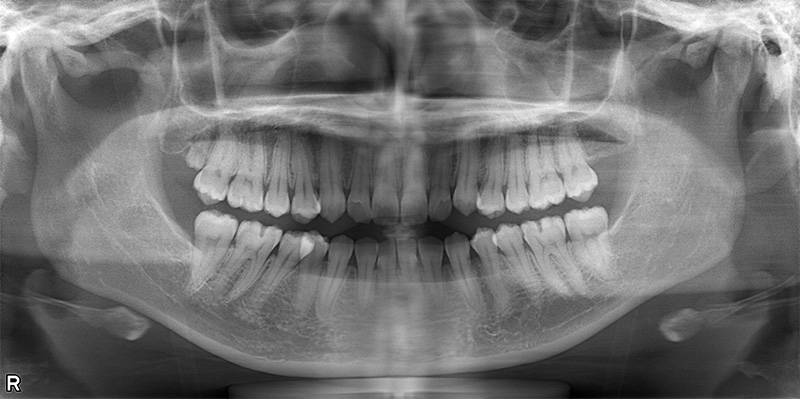

46歳女性

治療前